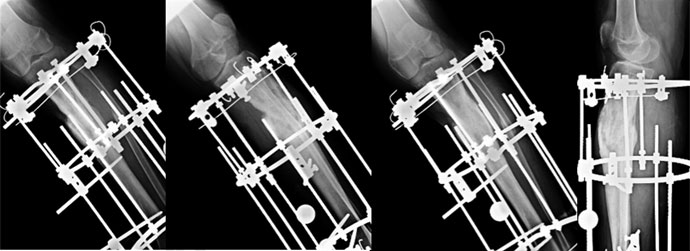

2 days after surgery

During the surgery an Ilizarov ring fixator was applied. The fibula was cut (red arrow) to allow compression at fracture site. Gradual compression was done and he was encouraged to bear full weight. |